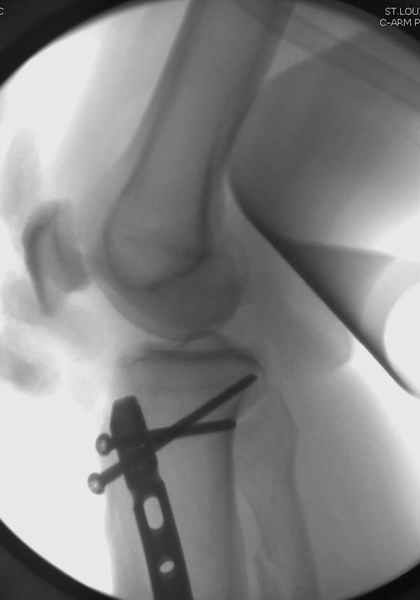

Здесь мы использовали новый Synthes Nail с дополнительными дырками, в проксимальной части 4: по две косых и поперечные (один стандартный а другой динамический), в дистальной части две поперечные, прямая и косая. Вес больного более 120 кг, нагрузку начнем через месяц.

Djoldas Kuldjanov, MD

St. Louis University Medical Center